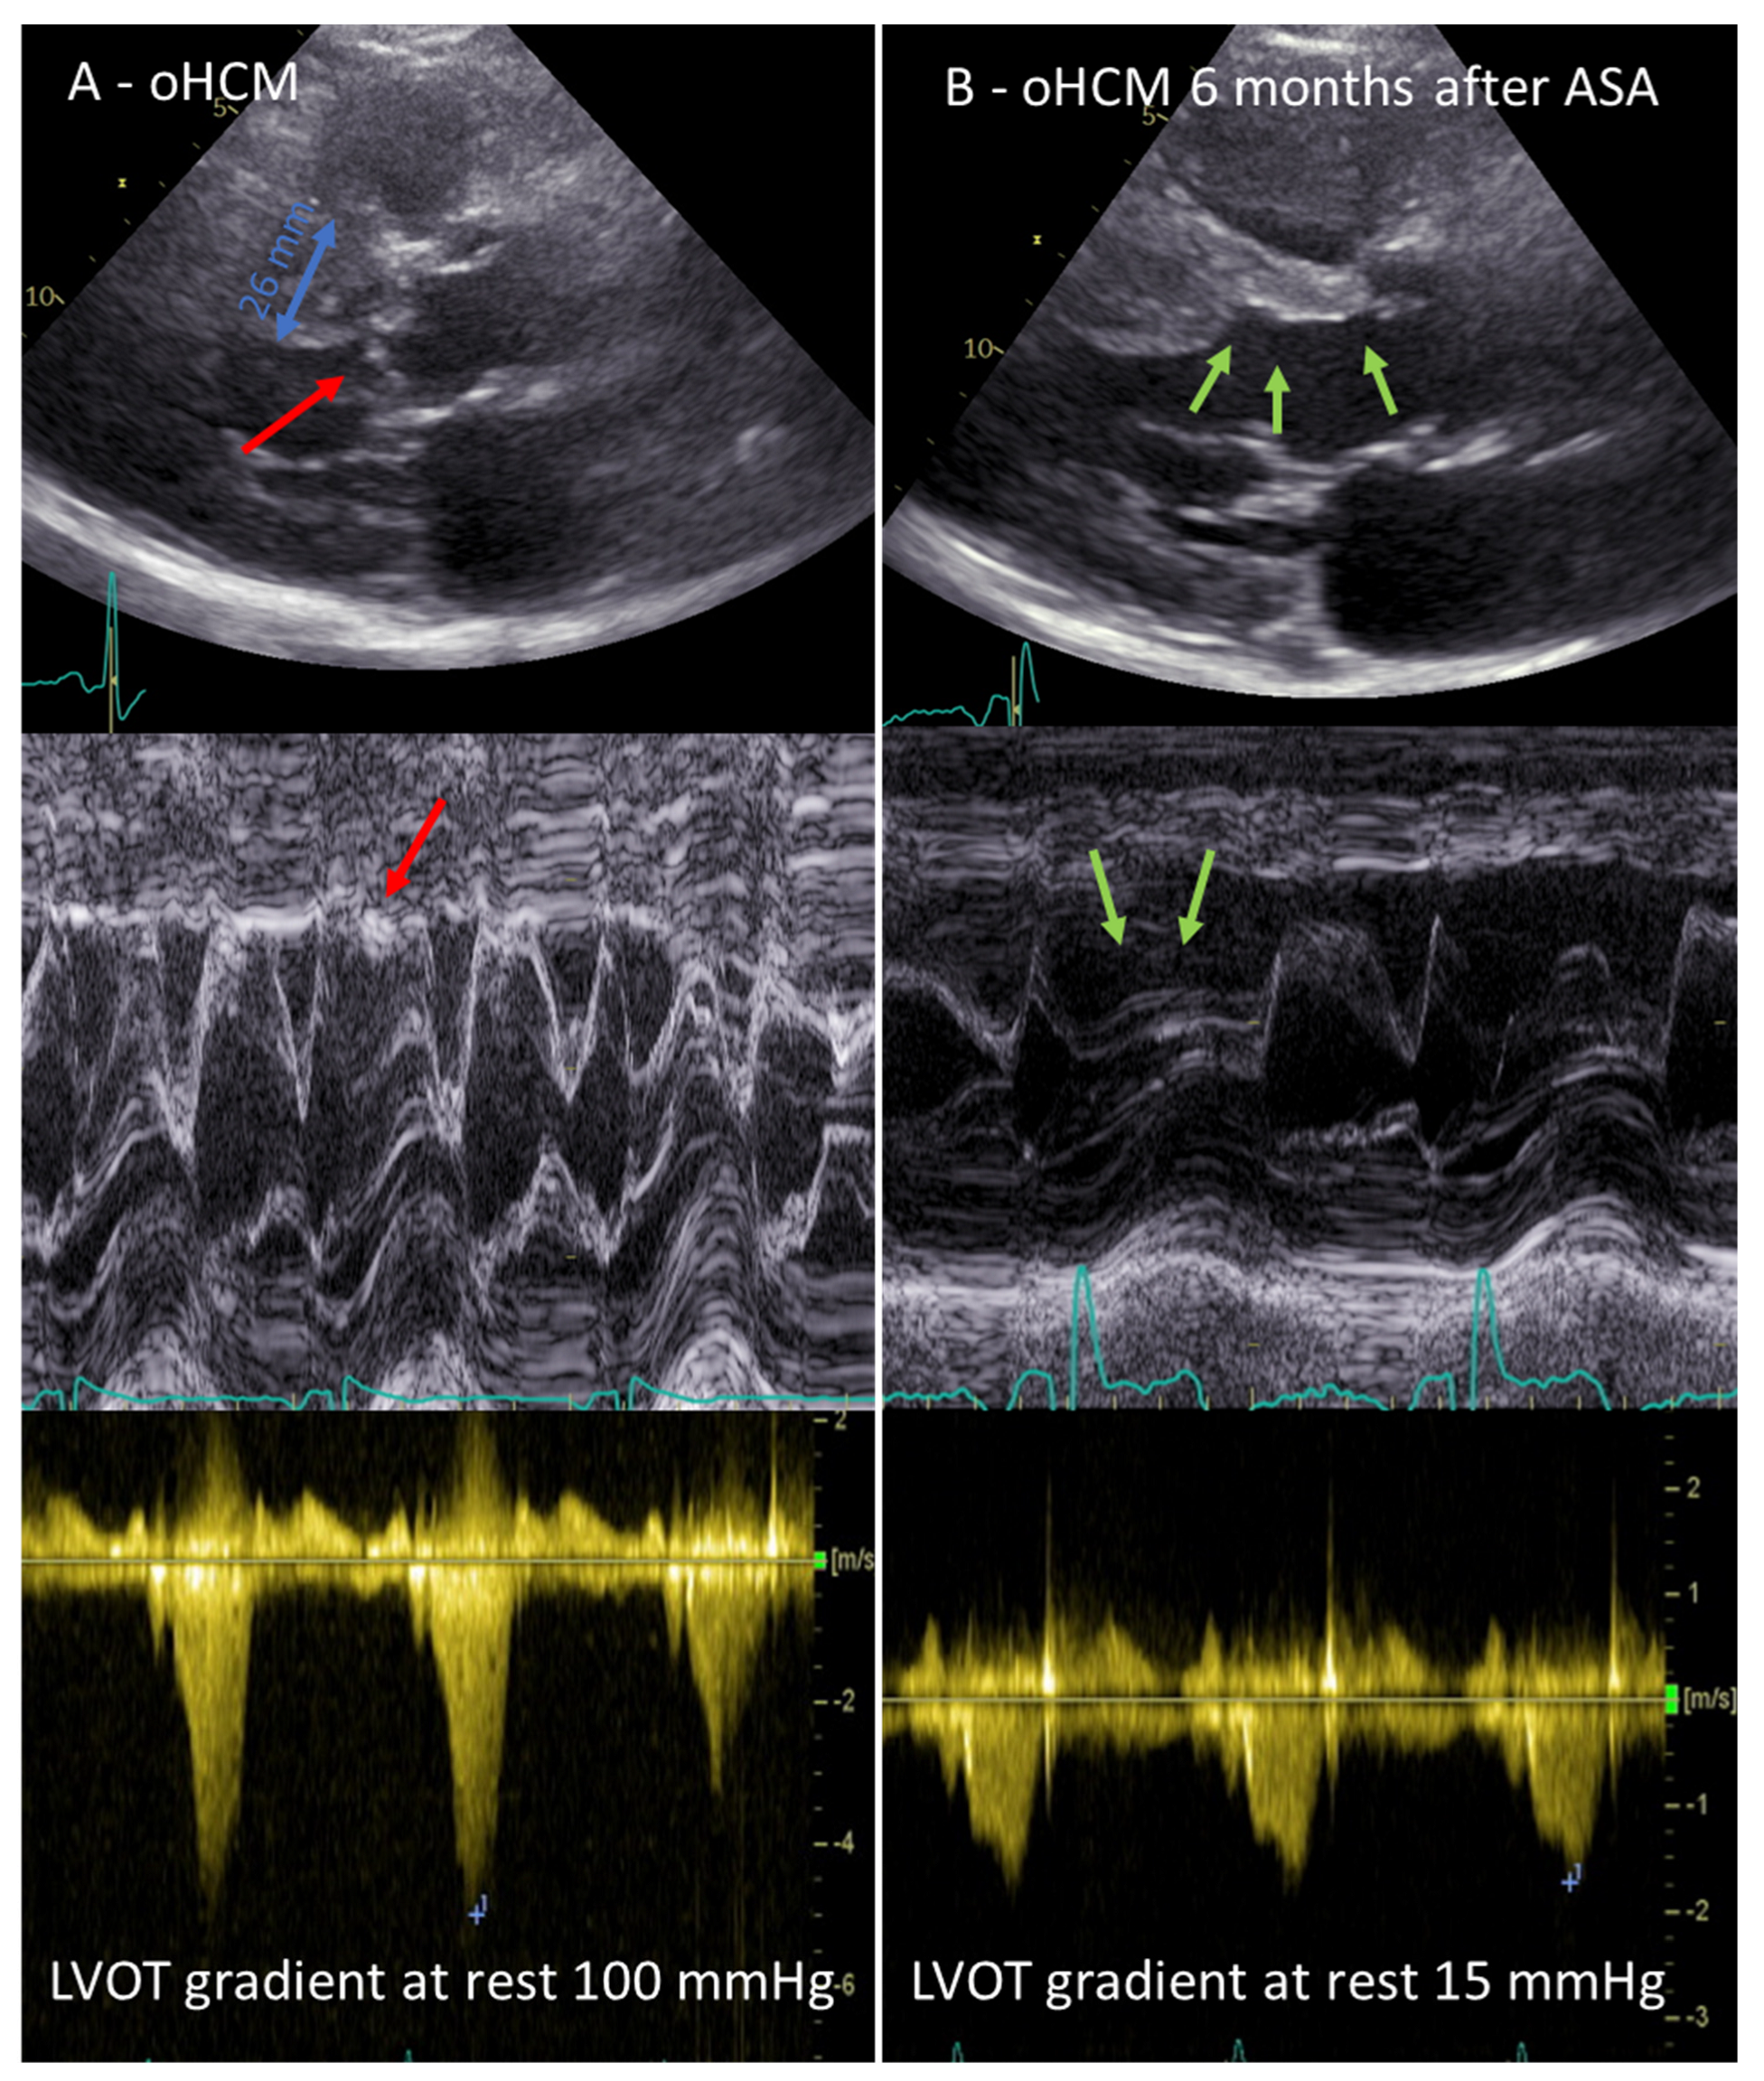

Coronary angiography can be performed at an earlier time or immediately before ASA to rule out concomitant coronary artery disease and to identify the septal branch suitable for alcohol injection. Femoral or radial access are both feasible and the choice is based on the operator’s preference. The standard Judkins left or extra backup guide catheter is engaged in the left coronary ostium. A right anterior oblique cranial view allows for good visualization of the left descending artery with its septal branches. In the majority of cases, the first septal artery originating from the proximal left anterior descending coronary artery (LAD) is the targeted branch; it is rare that the target branch derives from the first diagonal, circumflex, or right coronary artery. Myocardial contrast echocardiography has made an important contribution to the safety of the ASA procedure and was first described by L. Faber in 2004 [21]. After advancing a floppy guidewire and an over-the-wire balloon (OTW) into the target septal branch, the balloon is inflated at a low pressure and the occlusion of the target branch is confirmed by a contrast injection via a guide catheter and selective angiogram of the septal branch via the OTW balloon catheter lumen. This lumen is also used to inject 1–2 mL of an echocardiographic contrast agent (agitated gelantine polysuccinate, Gelafundin 4%, BBraun, Melsungen, Germany) to highlight the myocardial area supplied by the target branch. Simultaneous transthoracic echocardiography in multiple views allows for the verification of the target myocardial area for ASA. In case of contrast displacement (in, for example, the papillary muscle, right ventricular free wall, left ventricular apex, or lateral wall), the occluded septal branch is not suitable for ASA and another septal branch should be tested for suitability. The use of echocardiography to unmask the area supplied by the first septal perforator after contrast dye injection and thus visualization of the presumably infarcted myocardial area due to ASA can be considered the beginning of interventional-guided echocardiography. After confirmation of the correct septal branch by myocardial contrast echocardiography, 95% ethanol is infused very slowly via the balloon catheter lumen. The amount of ethanol is approximately 1 mL for each 10 mm of septal wall thickness. After 10 min, during which time an echocardiographic control with special focus on the wall motion and LVOT gradient is recommended, the OTW balloon can be deflated and retracted from the septal branch. A final angiogram should confirm a patent LAD and an occluded target septal branch (Figure 2).

Figure 2. Procedural steps of alcohol septal ablation. (A) Angiogram of the left coronary artery (red arrow indicates the first septal branch as the target for ASA); (B) Selective angiogram of the first septal branch, which is occluded with an over-the-wire balloon; (C) Myocardial contrast echocardiogram verifying the target region (arrows indicate the highlighted septal region); (D) Final angiogram of the left anterior descending coronary artery after alcohol injection (arrow indicates the occluded septal branch).